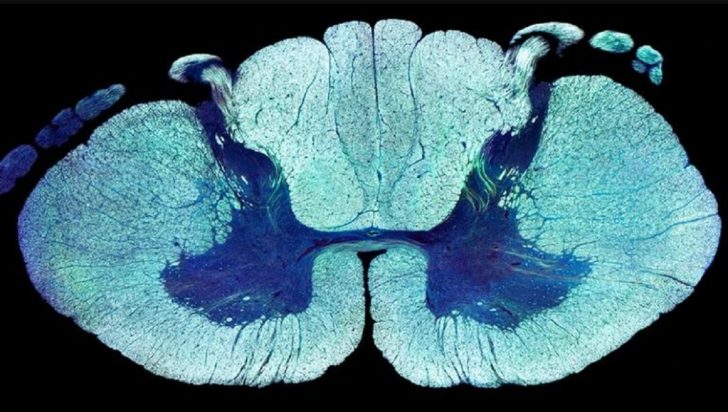

Όπως αναφέρει το ΑΠΕ, οι ερευνητές από την Ελβετία, τις ΗΠΑ, την Αυστρία και τον Καναδά, με επικεφαλής τον νευροεπιστήμονα δρα Γκρεγκουάρ Κουρτέν του Ελβετικού Ομοσπονδιακού Ινστιτούτου Τεχνολογίας (EPFL) στη Λοζάνη, οι οποίοι έκαναν τη σχετική δημοσίευση στο περιοδικό “Nature”, εντόπισαν – με πειράματα σε παράλυτα τρωκτικά και με τη βοήθεια τεχνητής νοημοσύνης – συγκεκριμένες ομάδες νευρώνων στο νωτιαίο μυελό που, αν διεγερθούν ηλεκτρικά, παίζουν ζωτικό ρόλο για να ανακτηθεί η δυνατότητα βάδισης.